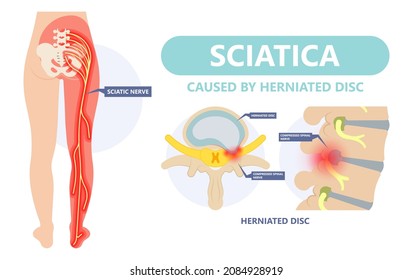

Download Sciatic nerve pain pictures